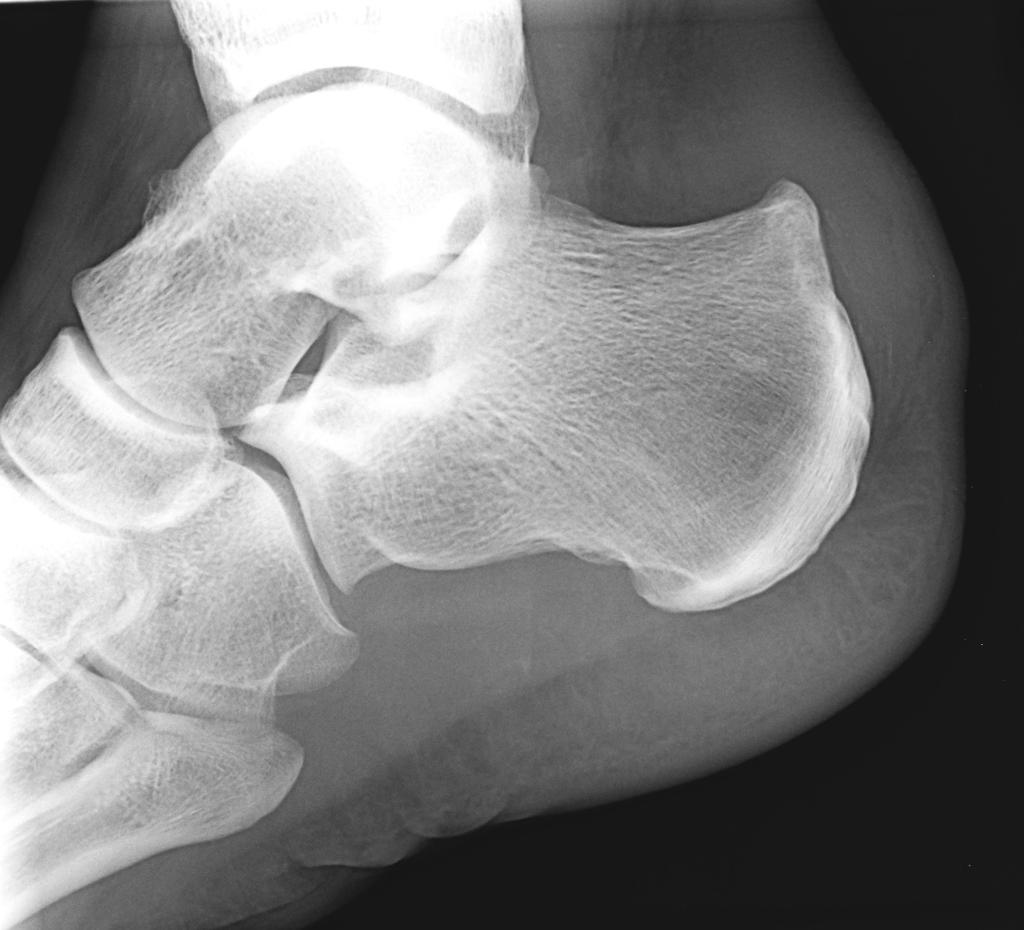

常规射线照相术的初步评估可能表明外观正常,但应特别注意侧位片上是否存在Stieda突或os三角。由于这些也常见于无后撞击综合征症状的患者,不一定引起撞击综合征;但是,在适当的临床背景下,它们可能有助于症状的产生。